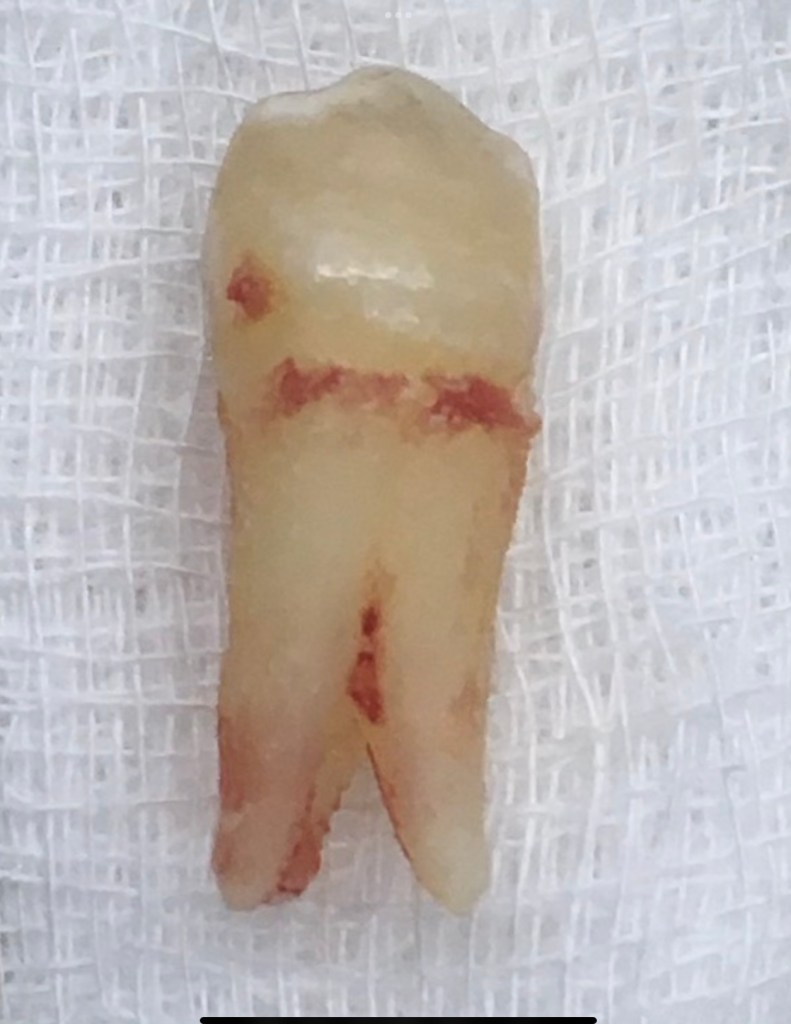

Don’t Remove. (before X-ray) radix-ento พบได้ในคนไทย 12.7% Germination X-ray ช่วยให้เห็นสิ่งที่ซ่อนอยู่ภายใน สังเกต furcation ก็รู้ว่าฟัน Perio Mermaid Premolar ให้สังเกตที่ mouth mirror เห็นถึงความฝ้ามัว เป็น Br พม่าครับ alloy ไม่แข็งมาก X-ray เท่านั้นจึงจะรื้อได้ ผมจะชอบวัดความยาวของฟันบ่อยๆ เทียบกับความยาวในใจที่เดาเอาไว้ RCT incomplete ใครสังเกตเห็นความผิดปกติบ้างครับ? ถึงกับต้องถ่ายทุกมุมเลยซี่นี้ remove ฟัน Crowding เป็น PVC ล้อมด้วยฟัน RCT อย่าลืม X-ray ก่อนถอนนะครับ Share this: Share on X (Opens in new window) X Share on Facebook (Opens in new window) Facebook Like Loading... Uncategorized